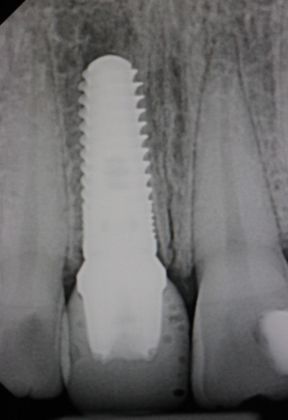

Dental Implants: Case 4

This beautiful girl presented to our Aiken office wanting to fix her front tooth. An immediate implant was placed and an immediate restoration was placed in its area. The smile was completed using an Emax implant crown much to the patient's satisfaction.